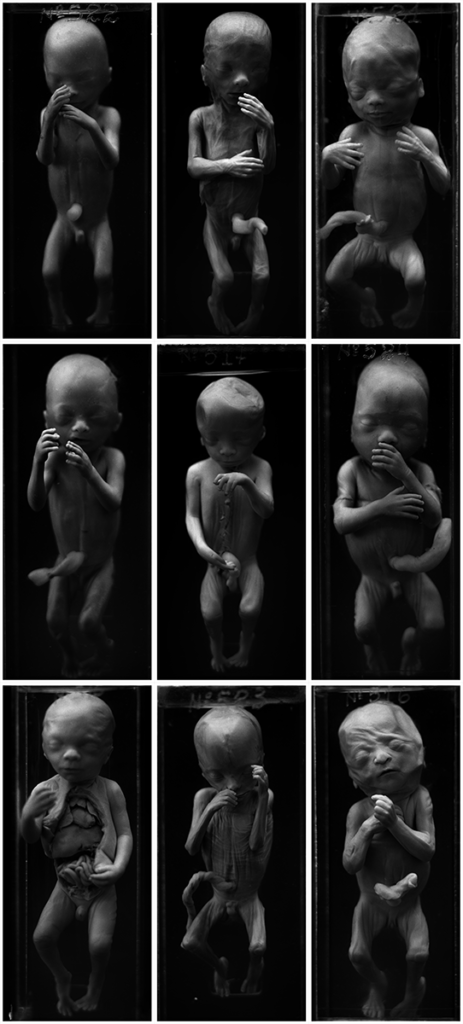

The OJardim series was created using a fictional storyteller that Daniel Malva imagined. The images have names which refer toarche types created by humanity to tell our story. The series has 25 images of human body parts dried or in formaldehyde solution. They were photographed at a collection of anatomy from São Paulo. This work was exhibited in São Paulo in 2015 and the works are in the process of being acquired by the City Museum of São Paulo.

series: OJardim

year: 2014

support: black and white 6×7 medium format film, Giclée on

Hahnemühle Photo Satin 310gsm

edition: 2/6 + 3 Ap

size: 67x55cm

year: 2014

support: black and white 6×7 medium format film, Giclée on

Hahnemühle Photo Satin 310gsm

edition: 2/6 + 3 Ap

size: 67x55cm

series: OJardim

year: 2014

support: black and white 6×7 medium format film, Giclée on

Hahnemühle Photo Satin 310gsm

edition: 2/6 + 3 Ap

size: 185x85cm

year: 2014

support: black and white 6×7 medium format film, Giclée on

Hahnemühle Photo Satin 310gsm

edition: 2/6 + 3 Ap

size: 185x85cm